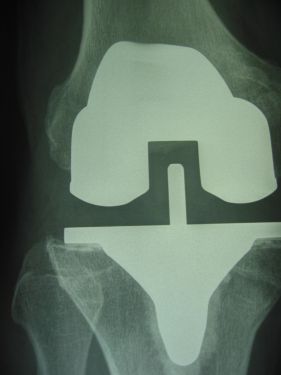

Chirurgie du genou

Prothèses totales ou partielles - nombre de poses en 2018 : 200...